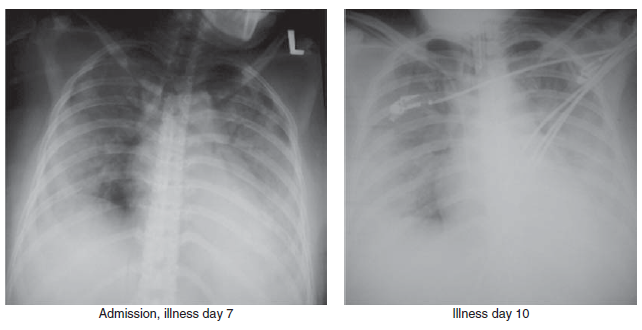

Meskipun hampir seluruh kasus H5N1 dibawa ke rumah sakit karena gejala demam, pneumonia dan hipoksia, presentasi gejala yang tidak biasa juga telah dilaporkan, seperti demam dengan diare, nausea, dan muntah [5], dan demam dengan diare, dan kejang-kejang yang melanjut menjadi koma dengan diagnosa klinis ensefalitis [59]. Durasi median dari onset penyakit sampai masuk ke rumah sakit pada 194 kasus H5N1 adalah 4 hari (kisaran 0 – 18 hari) [237]. Temuan laborairuym yang umum saat pasien pertama masuk rumah sakit meliputi leukopenia, limfopenia, trombositopenia ringan sampai moderat, dan meningkatnya transaminase [12, 201, 244]. Temuan radiografi bagian dada pada pasien H5N1 meliputi infiltrasi difus, multifokal, atau berbentuk pulau-pulau (patchy), inflintrasi interstitial, dan konsolidasi multisegmen dan lobular (Gambar 5.3 dan 5.4). Progresi sampai menjadi pneumonia bilateral dan kegagalan pernafasan yang memerlukan pemasangan mekanisme ventilasi invasif umum ditemukan. Komplikasi pada pasien H5N1 meliputi, ARDS, disfungsi multiorgan dengan penyakit ginjal dan jantung, dan koagulasi intravaskular terdissmeniasi (disseminated intravascular coagulation/DIC) dan sindroma shock mirip sepsis. DIC dan kegagalan multi organ telah dilaporkan pada kasus H5N1 pada wanita dengan kehamilan 4 bulan di China [183].

Gambar 5.2 Temuan radiografi bagian dada pada pasien wanita berumur 37 tahun yang terinfeksi fatal virus HPAI H5N1 clade 2.1. Konsolidasi bilateral lobus paru bawah dengan infiltrasi titik (patches) pada bidang paru bagian atas terlihat pada hari ke-7 perawatan. Meskipun telah menggunakan ventilasi mekanis, pasien akhirnya tetap mengalami sindrom kesulitan bernafas akut (ARDS) pada hari ke-10, dan meninggal di hari ke-11. Sumber: T.Uyeki, Centers for Disease Control and Prevention (CDC).